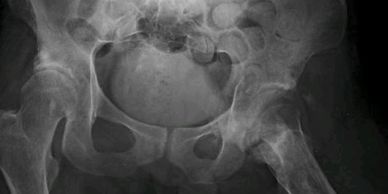

Mirá cómo recuperamos la movilidad en un caso de artrosis severa y deformidad acetabular mediante tecnología 3D de alta precisión. Planificación preoperatoria en 3D para cirugía de cadera con artrosis severa e importante deformidad acetabular. Se imprimieron biomodelos en 3D y guías para la correcta colocación de los componentes protésicos. De esta manera, se logró restaurar la longitud de las piernas y se eliminó el dolor invalidante que presentaba el paciente.

Cirugía compleja de reemplazo total de cadera.

Paciente con artrosis severa y deformidad ósea que dificultaba la colocación acetabular. Con tomografía realizamos planificación 3D y diseñamos una guía quirúrgica personalizada impresa en 3D. En quirófano replicamos el plan: posicionamiento preciso del componente y restauración del centro de rotación. La tecnología 3D aporta más precisión, seguridad y predictibilidad en casos complejos.